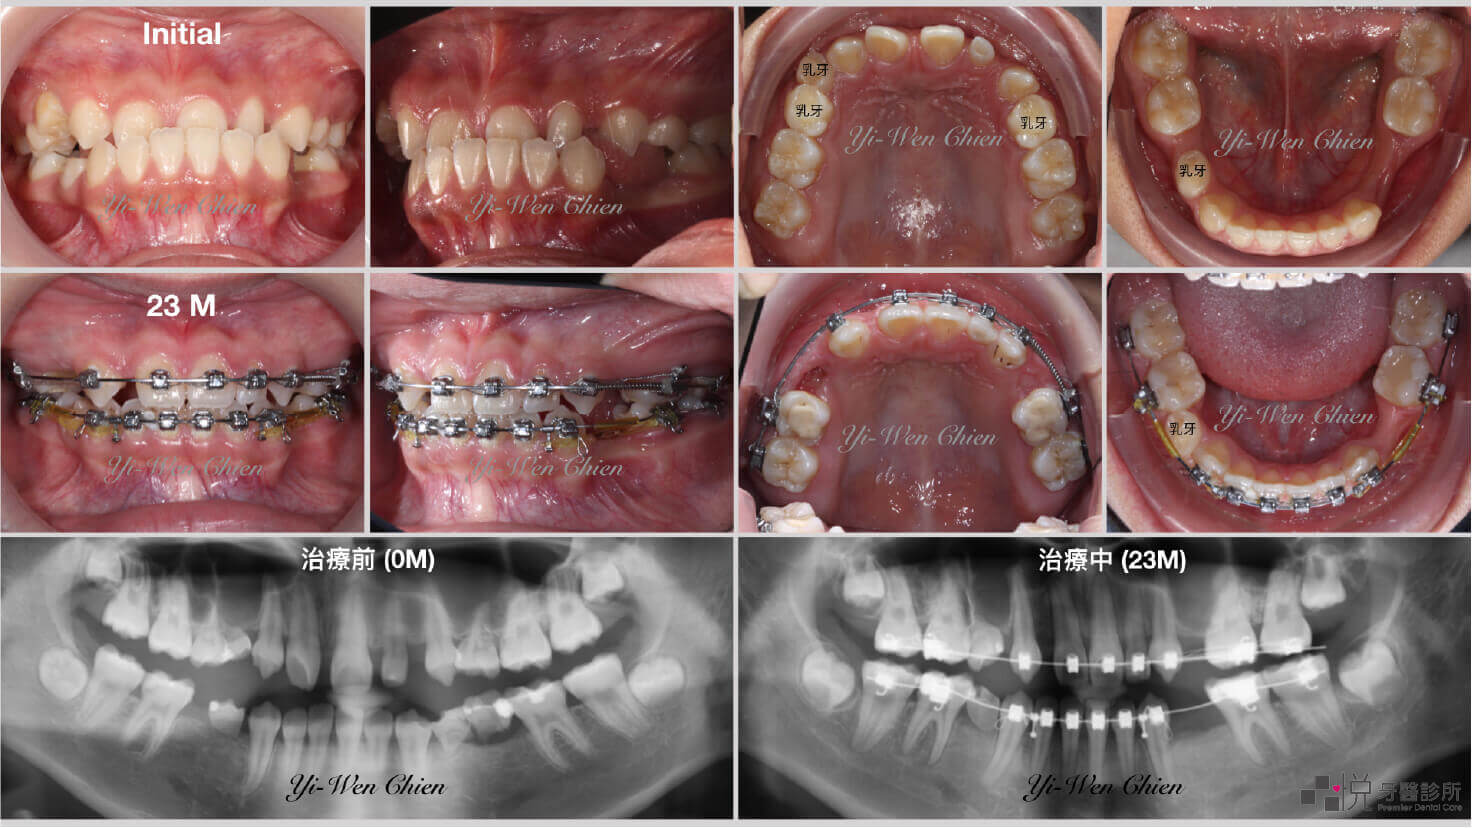

本案例治療前右上、右下、左下第一大臼齒缺失許久,下顎兩側第二大臼齒和智齒往前傾倒。右下第二大臼齒嚴重傾倒,牙周狀況差,拔除後開始矯正治療。

智齒補缺牙案例二

下顎兩側智齒往前取代⾅齒,並合併植牙贋復

案例提供:錢怡雯醫師

在沒有使用骨釘的輔助下,三顆傾倒的大臼齒皆已扶正,關閉右上和左下的缺牙空間,右下預留空間待矯正後植牙贗復。